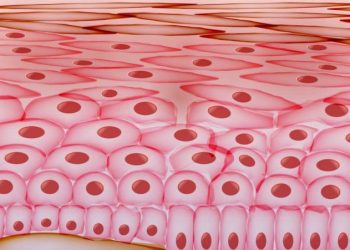

Read moreבעיות עור כל מה שחשוב לדעת אורן זריף הפורטל הרשמי

אורן זריף מטפל באנשים למעלה מ-25 שנה למרות ההצלחות הרבות חשוב לציין כי הטיפול אינו רפואי ואינו מהווה תחליף לרפואה...